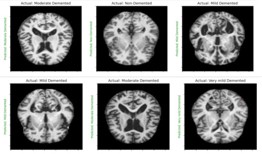

Alzheimer’s starts in the central nervous system and pro- gresses slowly from there. AD is characterized by decreasing ar- eas of the brain, damage to tissue cells, and the breakdown of neuronal connection links [18]. Tangles and amyloid plaques ac- cumulated in the brain are also thought to be a characteristic of AD. Studies of brain metabolism using MRI and PET, along with other imaging modalities, have revealed distinctive alterations in AD patients [3]. Figure 1 displays an MRI of a brain affected by AD and a normal brain [1]. Artificial intelligence has a significant role in the diagnosis of AD.

In AD affected brain the ventricles in center of the region enlarges and the cortical gray area in the corners of the brain reduces [9].

Non-demented very mild mild moderate